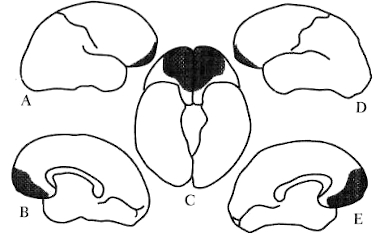

Figura 2-4. A = diagrama de la arquitectura celular de la corteza cerebral con su característica formación por capas; B = diagrama de la arquitectura celular de los núcleos.

La estructura que ha provocado el mayor esfuerzo investigador de la neurociencia es la corteza cerebral. Puede ser visualizada como un manto cobertor, que abarca toda la superficie del cerebro, incluyendo la que está en la sima de las grietas conocidas como cisuras y surcos, que dan al órgano su característico aspecto plegado (ver Fig. 2-2). El espesor de esta manta de milhojas es cercano a los tres milímetros; las capas son paralelas unas con otras, y con la superficie del órgano (ver Fig. 2-4). Toda la materia gris por debajo de la corteza (núcleos —grandes y pequeños— además del córtex cerebelar) se llama subcortical. La parte más moderna es conocida como neocorteza, en tanto que la porción arcaica se denomina corteza límbica (ver figura 2-5). A lo largo del libro me referiré a corteza cerebral (neocorteza) o a corteza límbica y a sus partes específicas.

La figura 2-5 es un mapa de uso frecuente, basado en las áreas citoarquitectónicas (regiones de arquitectura celular distintiva) de la corteza cerebral. Se conoce como Mapa de Brodmann y las zonas están designadas con números.

Figura 2-5. Mapa de las principales áreas que identificó Brodmann en sus estudios de arquitectura celular (citoarquitectura). No es una cartografía frenológica ni un mapa moderno de las funciones del cerebro, sino sólo una referencia anatómica conveniente. Algunas áreas son demasiado pequeñas y no se las puede describir aquí, o se esconden en las grietas. La imagen superior muestra la zona externa del hemisferio izquierdo; la inferior, el aspecto interno.

Una parte del sistema nervioso central a la que me referiré frecuentemente es tanto cortical como subcortical y se llama sistema límbico. (Término comodín para una variada colección de estructuras evolutivamente arcaicas; a pesar que muchos científicos se niegan a usarlo, resulta ocasionalmente práctico). Las estructuras principales del sistema límbico son la corteza cingular (cingulate gyrus), en la corteza cerebral, y dos series de núcleos: la amígdala y el prosencéfalo basal.